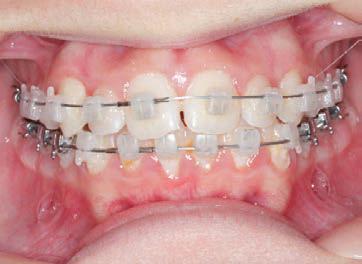

CLASS II DIV.1 - Marra

INITIAL - 4/4/18

PROGRESS 1 - 26/9/18 - Class I platform accomplished in 5.75 months with Motion 3D COLOR Appliance

PROGRESS 2 - 26/9/18 - Placement of the SLX 3D Clear Brackets